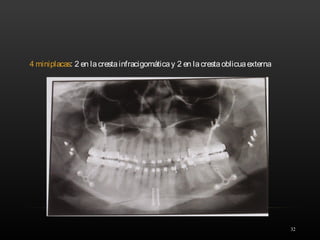

4 miniplacas: 2 en lacrestainfracigomáticay 2 en lacrestaoblicuaexterna